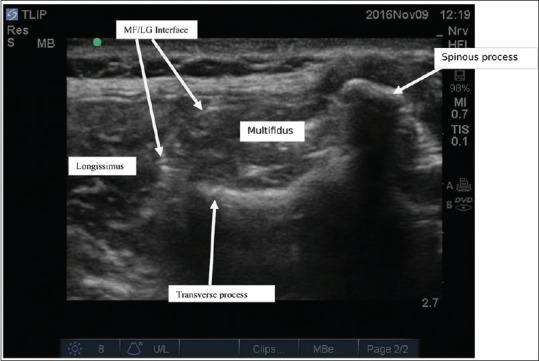

Ultrasound-guided thoracolumbar interfascial plane block for spine surgery.

Saudi J Anaesth. 2017 Apr-Jun;11(2):248-249. doi: 10.4103/1658-354X.203052.